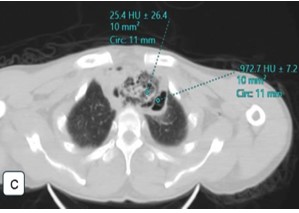

Boerhaave syndrome (BS) is a rare, life-threatening condition characterized by spontaneous esophageal rupture, commonly triggered by forceful vomiting. Due to its nonspecific presentation, BS is often misdiagnosed, leading to delayed intervention and high mortality. We report a case of BS presenting with hematemesis, respiratory distress, and collapse, emphasizing the forensic implications and the role of postmortem computed tomography (PMCT) in virtual autopsy. A 46-year-old male with a history of alcohol consumption experienced sudden-onset hematemesis and respiratory distress, followed by cardiopulmonary arrest. Despite resuscitation efforts, the patient was pronounced dead. Autopsy findings revealed a full-thickness esophageal rupture with mediastinal contamination and pleural effusions, confirming BS as the cause of death. PMCT successfully detected pneumomediastinum, free intrathoracic air, and mediastinal fluid, demonstrating its utility in forensic investigations. The case highlights key differential diagnoses of sudden death, including acute myocardial infarction, pulmonary embolism, and aortic dissection. This case aligns with existing literature where hematemesis, though less commonly reported, was a significant symptom preceding cardiovascular collapse. Delayed diagnosis of BS remains a critical factor contributing to poor outcomes and increased mortality rates. The integration of PMCT with conventional autopsy enhances the diagnostic accuracy of esophageal perforation-related deaths, particularly in forensic settings. Comparative analysis with previously reported cases underscores the need for heightened clinical suspicion and early imaging to prevent fatal outcomes. Boerhaave syndrome remains a diagnostic and therapeutic challenge, often leading to sudden and unexpected death. This case reinforces the medicolegal importance of virtual autopsy in identifying esophageal rupture, particularly in unwitnessed or unexplained deaths.